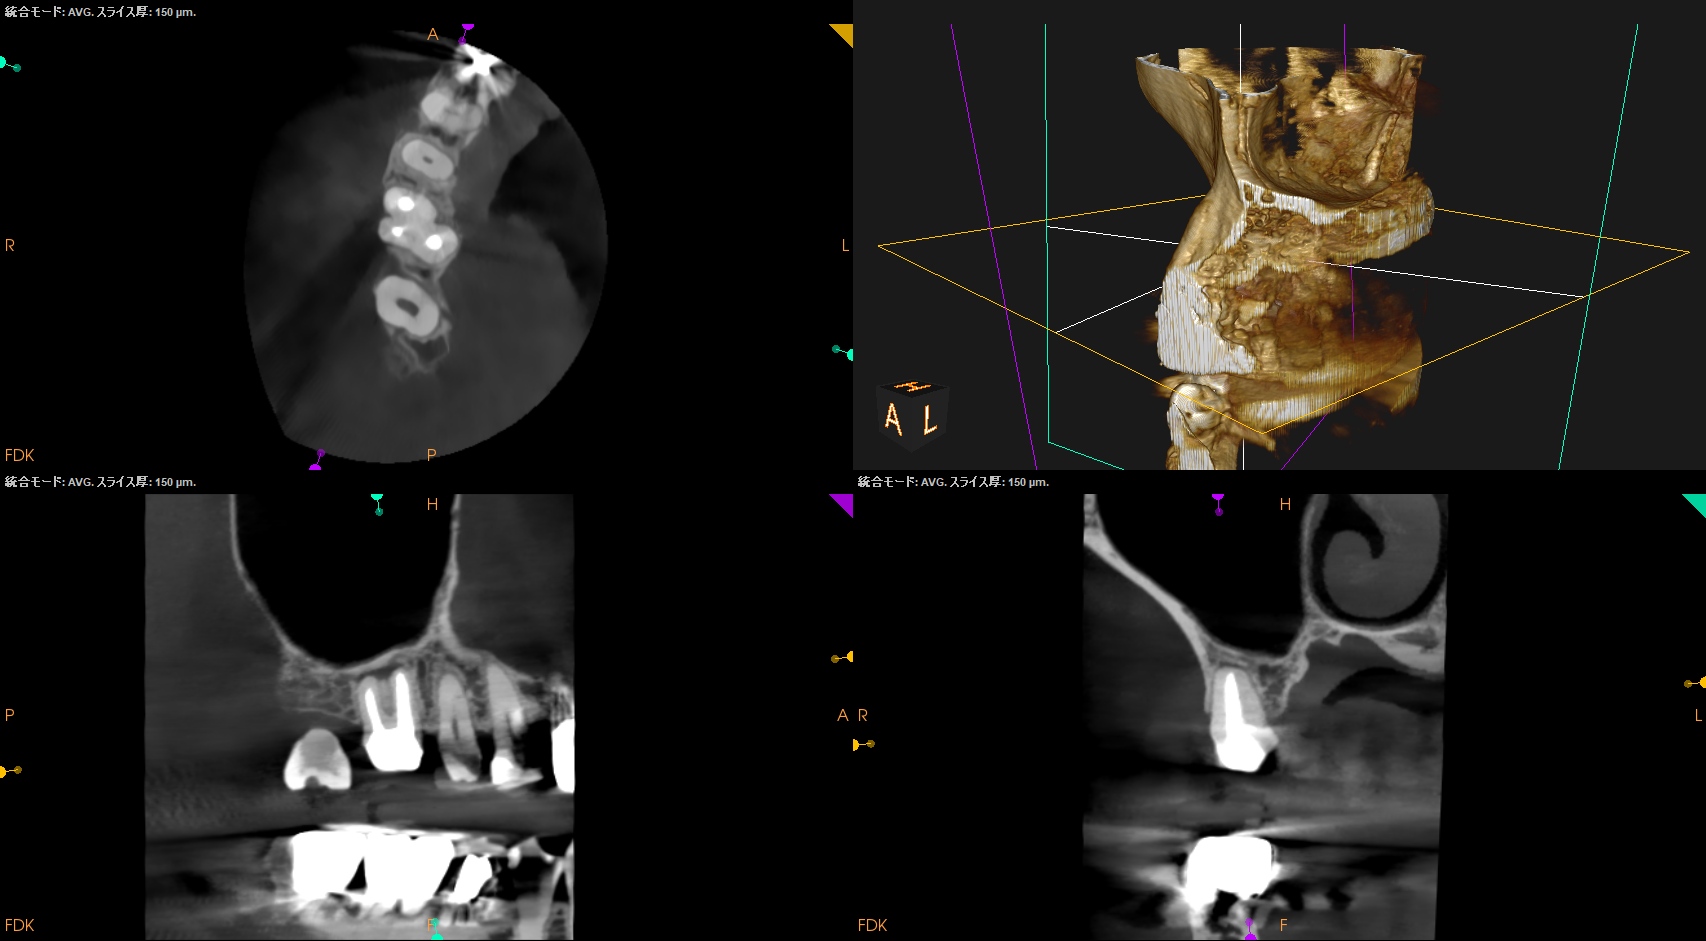

CBCT(2024.7.1)

#3

MB

DB

P

MB,DB,Pと3根全てに病変がある。

しかも形成が不完全だ。

再根管治療が濃厚である。

#14

MB,DBには病変がないが、Pに存在する。

これは頭が痛い。

パラタルフラップも困難なケースだからだ。

#16